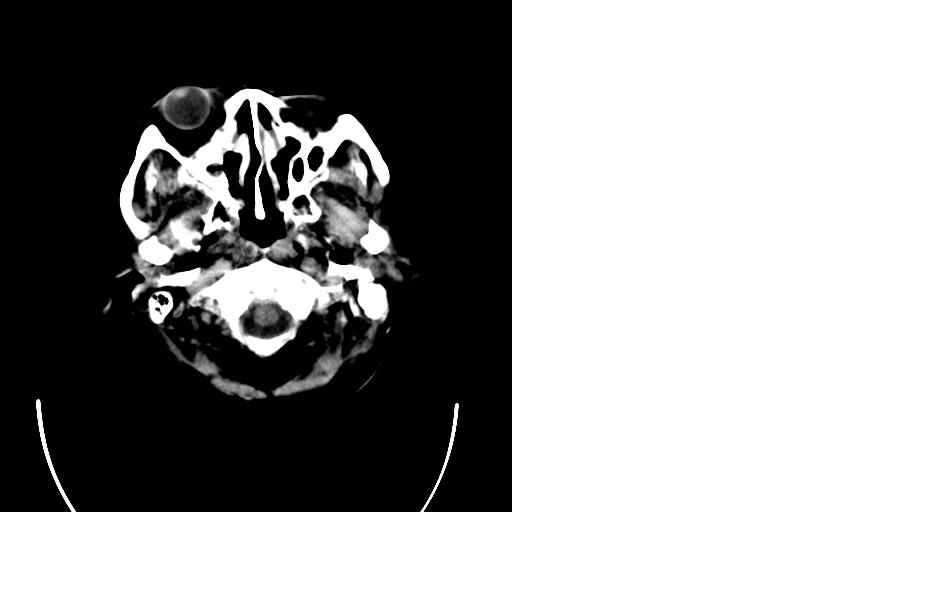

女,77岁,渐进性突眼2年,无其他明显症状

右侧额部软组织密度肿块,界限不清,明显向前下方增长,占位效应明显,内见钙化,局部颅骨明显吸收.考虑:右额叶脑膜瘤.建议:增强

右额窦粘液囊肿,向前累及筛窦并进入眼眶使眼球前突;向下进入颅内右额叶脑质及侧脑室受压

向前、后破坏颅骨,向后进入颅内,下破坏眶上板进入眶窝,压迫眼球前移,向前内破坏筛窦。

支持:病变的起源我乐意定在右额窦。右额窦粘液囊肿或粘液腺癌累及筛窦、眼眶使眼球前突;向下进入颅内右额叶脑质及侧脑室受压变形。

右侧筛窦类圆形实质性肿块向颅内呈膨胀性生长,边缘较为光滑,其内似见囊性低密度影,边缘骨壁受压变薄移位,部分骨质缺损破坏

定位:来源右额窦。定性:良性占位—额窦黏液囊肿。理由1、病灶中心位于右额窦区,侵及筛窦并向下向前压迫眼球2、骨质呈膨胀性改变,骨质弓形变薄但骨壳完整,如为恶性骨质应为侵蚀性破坏3、黏液囊肿好发于筛窦、额窦。